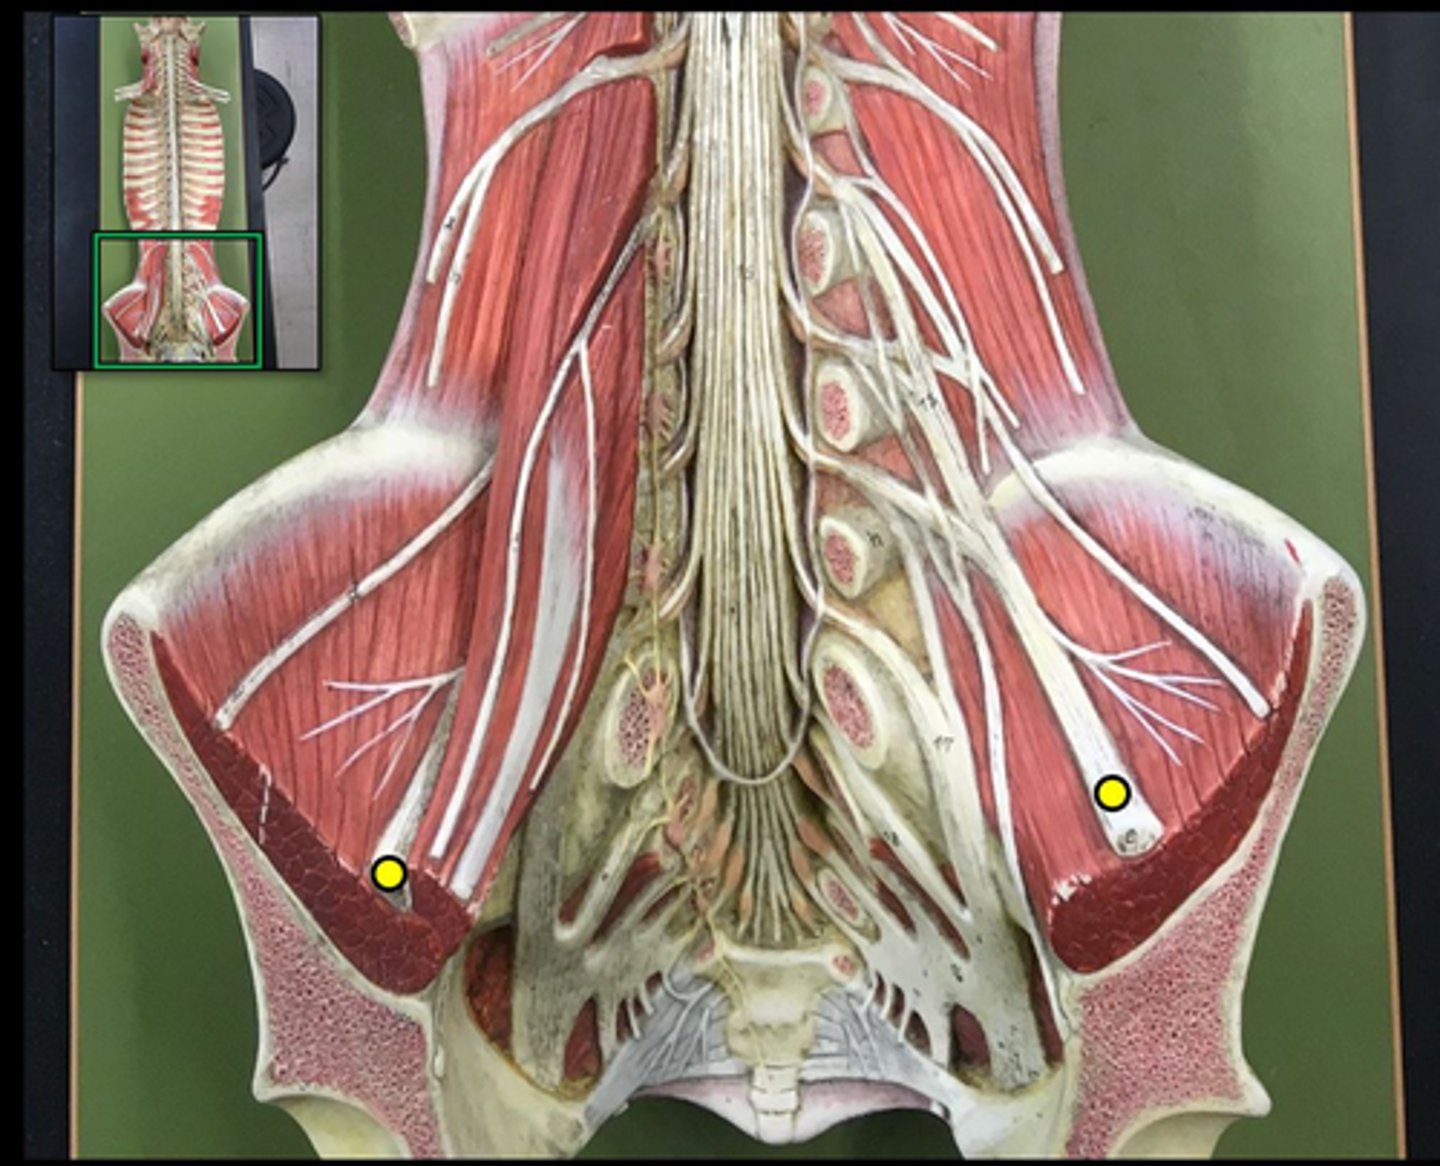

posterior root

axons of sensory neurons

posterior root ganglion

anterior root

axons of motor neurons

spinal nerve

cauda equina

bundle

lumbar plexus

T12- L4

sacral plexus

L4- S4